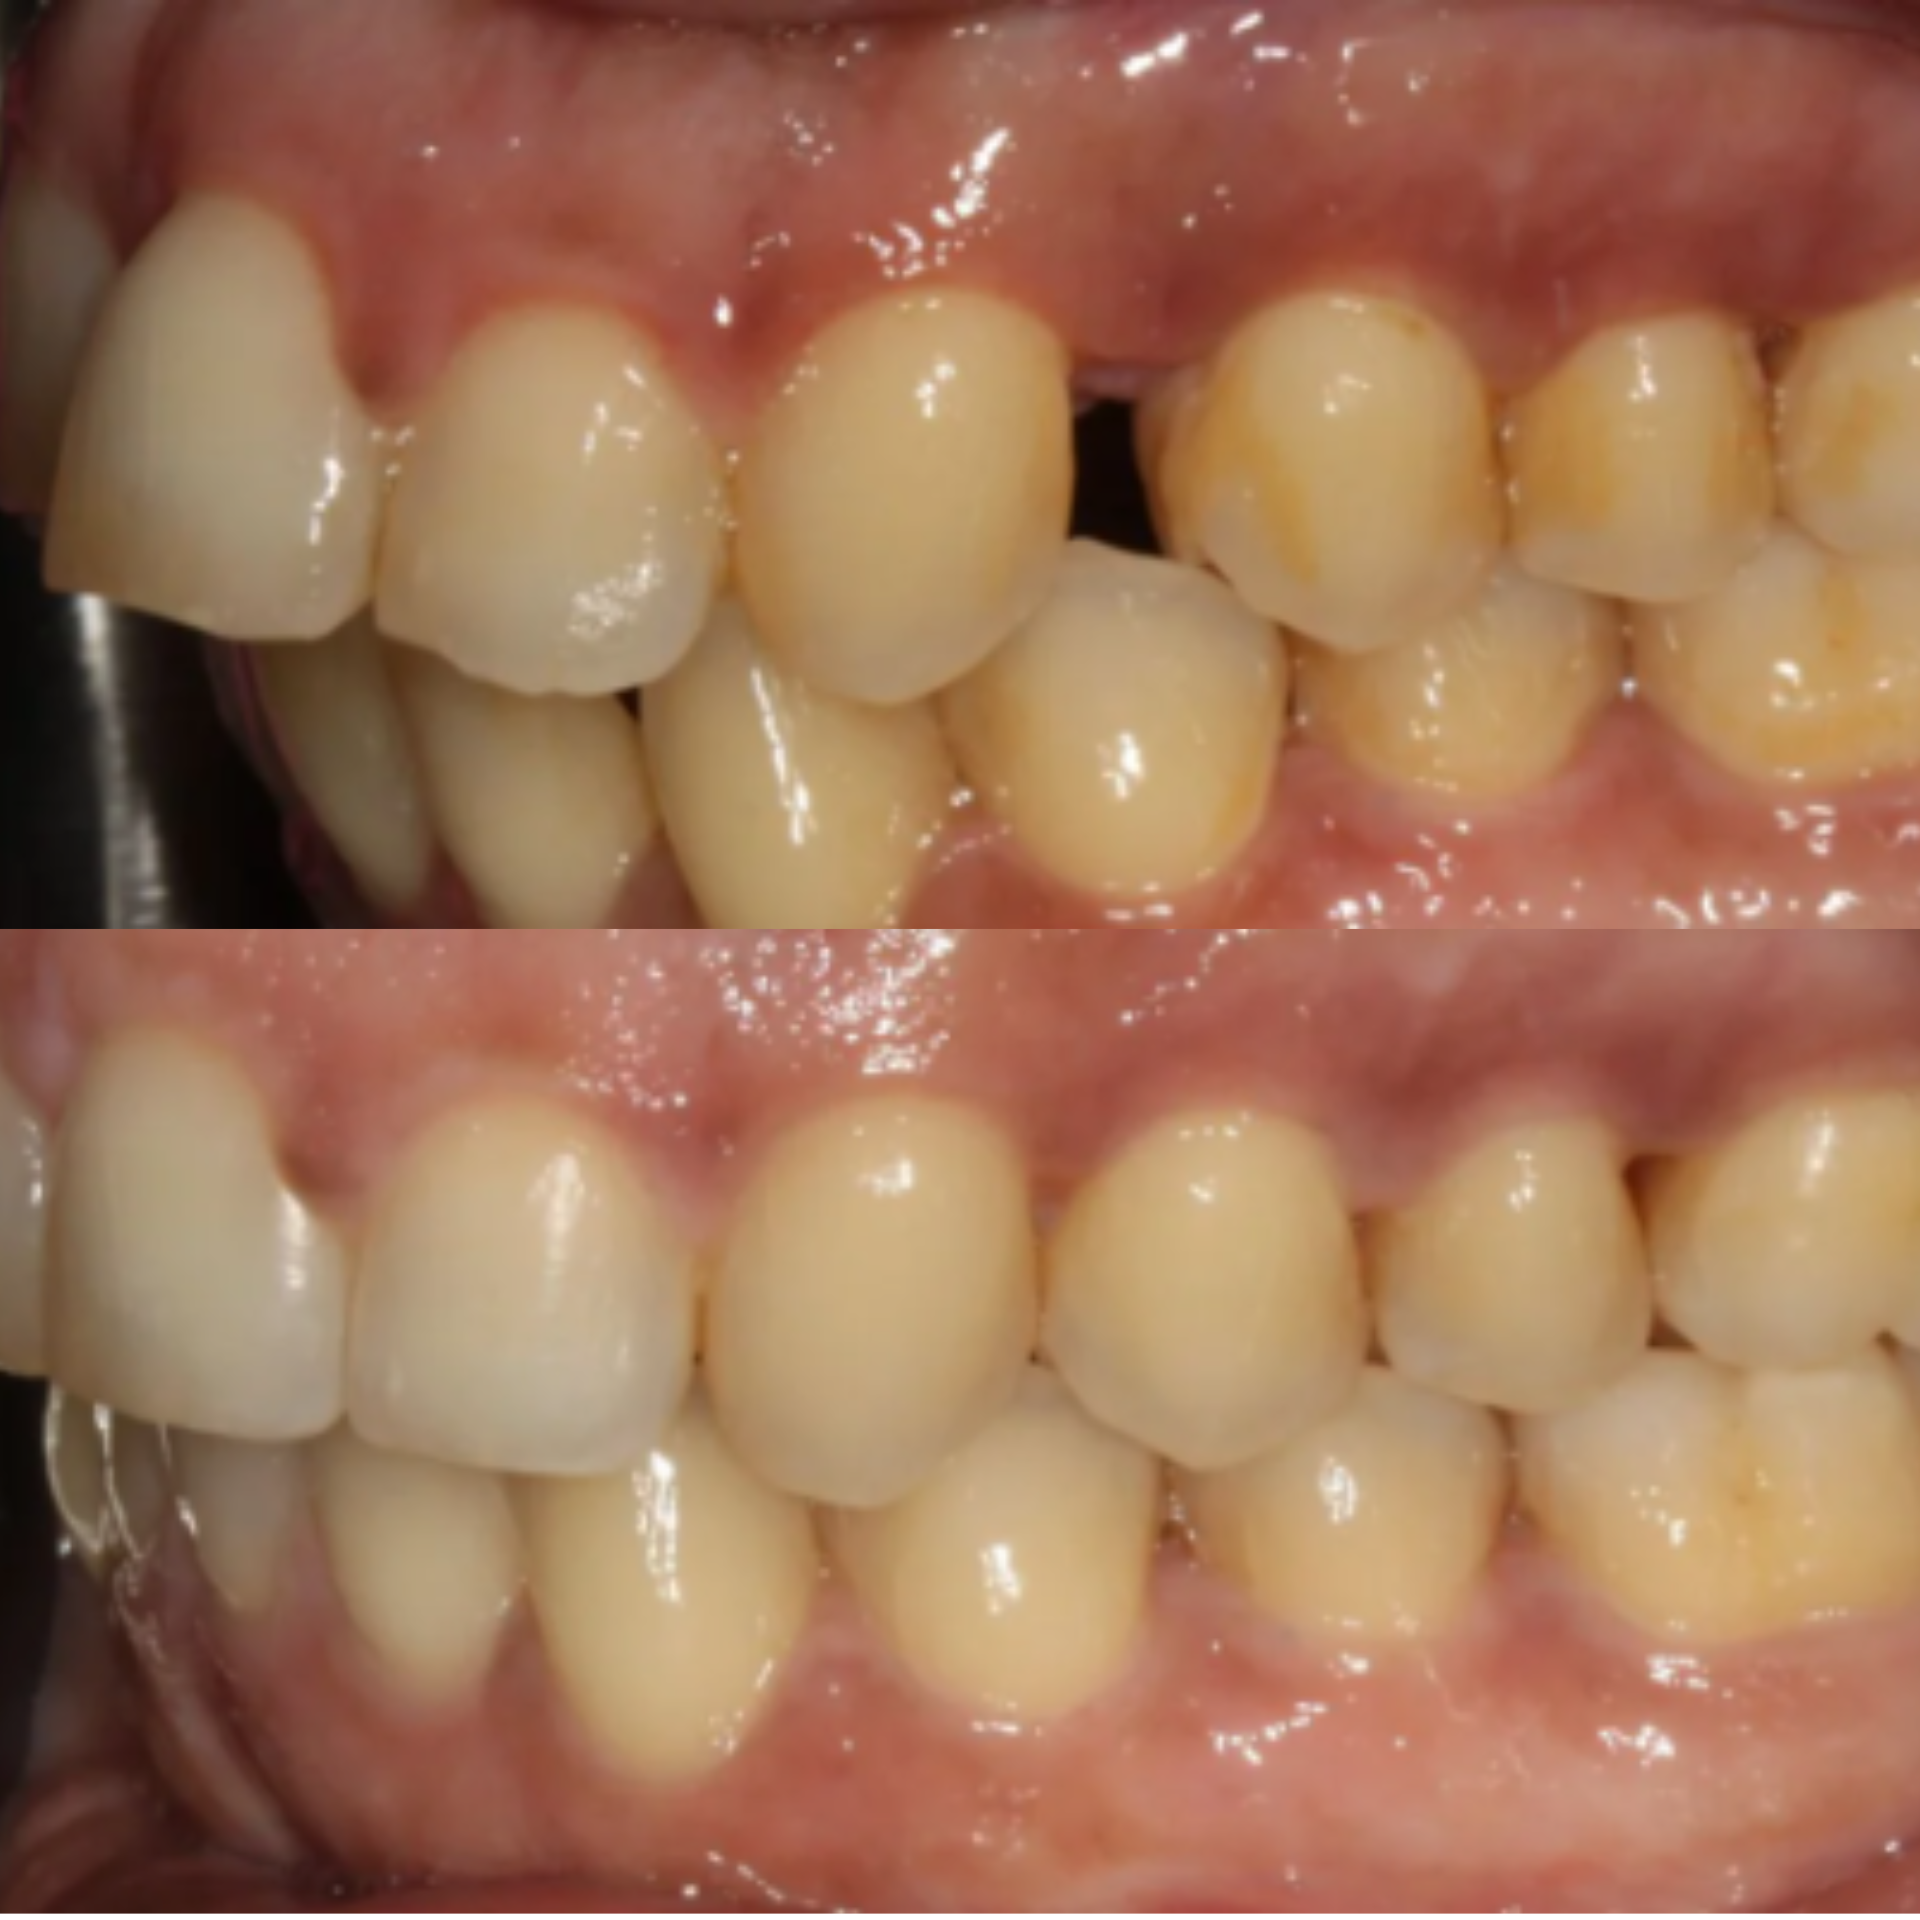

This patient presented with significant gum recession affecting the right central tooth, which ultimately required extraction.

Our team carefully planned and executed the placement of an implant supported crown to achieve a natural looking, fully functional esthetic result. The final outcome not only restored the patient’s smile, but also renewed their confidence.